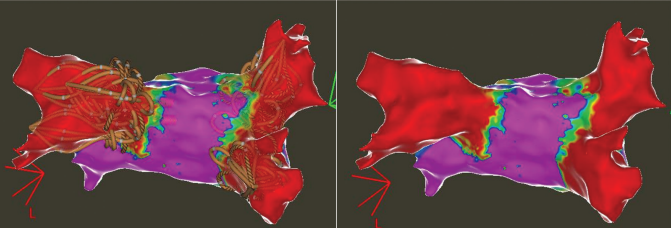

diagnosed 1.5 years prior. He was previously cardioverted and maintained on dronedarone with recurrence of symptomatic persistent AF, prompting referral for catheter ablation. He subsequently underwent AF ablation utilizing a pentaspline catheter. Ultrasound guidance was utilized to obtain 3 points of vascular access in the right femoral vein (Figure 1). ICE guidance was utilized for transseptal access and to guide catheter manipulation while ensuring optimal contact with ablation (Figures 2 and 3). Meticulous sheath management was employed, ensuring performance of all sheath exchanges while aspirating to reduce likelihood of air bubble introduction. A baseline electroanatomic voltage map was obtained for a substrate-based approach, which showed a predominantly healthy left atrium despite persistent AF though notably early in its course (Figure 4). There was spontaneous induction of AFL with a cycle length of ~280 ms and response to entrainment and activation mapping most consistent with typical AFL. The decision was made to proceed with PV isolation with confirmation of antral level isolation without significant encroachment on the posterior wall on a post-ablation voltage map (Figure 5). The cavotricuspid isthmus line was outlined on the EAM system with ICE while ensuring the intended ablation path was not in direct proximity to the right coronary artery. Ablation was then performed utilizing the pentaspline catheter in flower configuration after pre-administration of nitroglycerin and phenylephrine with termination of AFL and demonstration of bidirectional block post ablation. Total fluoroscopy time was ~4 minutes, the majority of which was utilized for the typical flutter ablation. The patient tolerated the procedure well and was discharged home 6 hours later. He continues to do well in outpatient follow-up.

Highlighted in this case are key tenets in our procedural approach to PFA. First, similar to other ablation technologies, the majority of complications are usually vascular in origin. These complications are largely mitigated with appropriate ultrasound guidance technique to vascular access, as was demonstrated in the MANIFEST-17k registry.16 The need for meticulous sheath management to reduce air bubble introduction cannot be overstated given the large sheath profiles utilized, to reduce the risk of stroke and coronary air embolism. We maintain that ICE guidance and EAM play a pivotal role in guiding ablation. This is important to ensure adequate contact for optimal energy delivery as there is increasing data highlighting its importance for durability.17

Additionally, the ease of ablation with these large footprint PFA catheters also raises concern of collateral damage to neighboring healthy myocardium such as the posterior wall when perhaps only PVI is the intent. This effect in some instances can be proarrhythmic. The ability provided by these tools comes with significant responsibility to be judicious with ablation lesions which can certainly be better optimized with EAM and ICE guidance. The clinical impact of this will likely be better delineated as we have large-scale, long-term follow-up data. Additionally, ICE and EAM guidance also facilitate a low or no fluoroscopy workflow as there is more data being published on the feasibility of this approach.18 This builds upon the significant trend towards zero-fluoroscopy procedures with thermal ablation platforms, which impact both the patients and EP team.